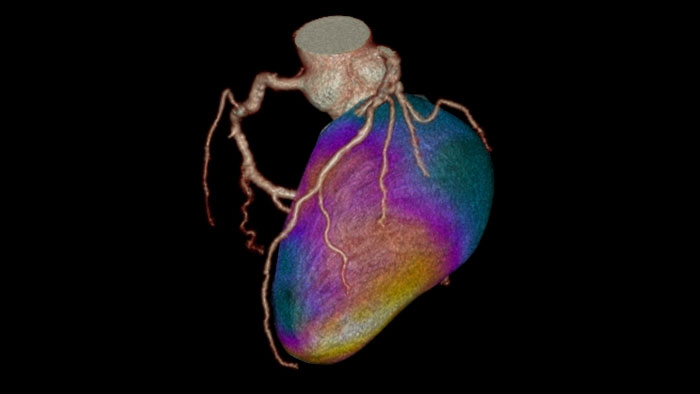

Dynamic color maps provide an assessment of myocardial risk

This application supports visualization, diagnostic assessment, and quantification of cardiac images focusing on the left ventricular myocardium: specifically providing quantitative myocardial blood flow measurements for CT images, including the ability to identify areas of decreased perfusion within the myocardium that may represent ischemia. The application supports axial, ECG-gated CT images, consisting of multiple time shots of the same myocardial region over time. CT Dynamic Myocardial Perfusion displays the results as a composite image (single image that is calculated from a set of time course images at a single location).